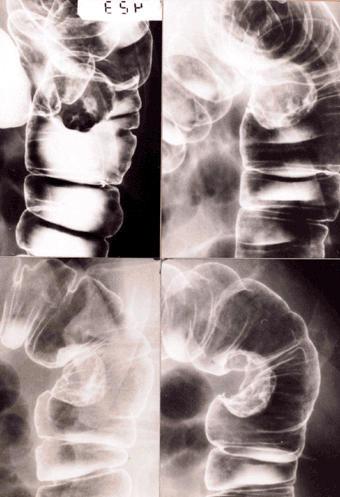

[Image-ID:402]

질환(병리주체)의 분류 악성 상피성종양/선암

부위(장기별) 대장/S상

검사방법 X-P

종양의 육안분류 1형(종괴형)/

종양의 최대경(밀리미터) 30~34

종양의 심달도 ss(a1)